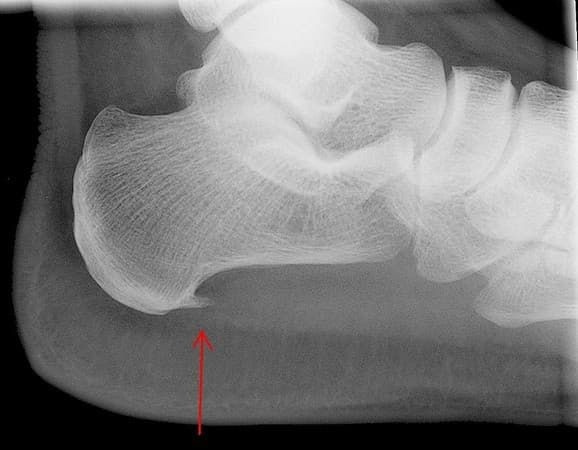

Пример визуализации пяточного остеофита на рентгеновском снимке ступни

На самом же деле этим названием именуют очень распространенное патологическое состояние, сопровождающееся образованием костного выроста (экзостоза), напоминающего по своей форме и расположению шпору на ковбойских сапогах, на пяточной кости и болями в области ступни. Но причина болей при этом заболевании, вопреки всему совсем в другом. Давайте попробуем разобраться.

Вырост на пяточной кости непосредственно сама «шпора» — это особенность строения пяточной кости некоторых людей, которая может появляться с течением жизни, и которая, как правило, не является изначальной причиной боли и воспаления подошвенной фасции, но может усугублять ее течение, дополнительно травмируя данную структуру. Способствует появлению данной анатомической особенности хроническая микротравматизация плантарной фасции.